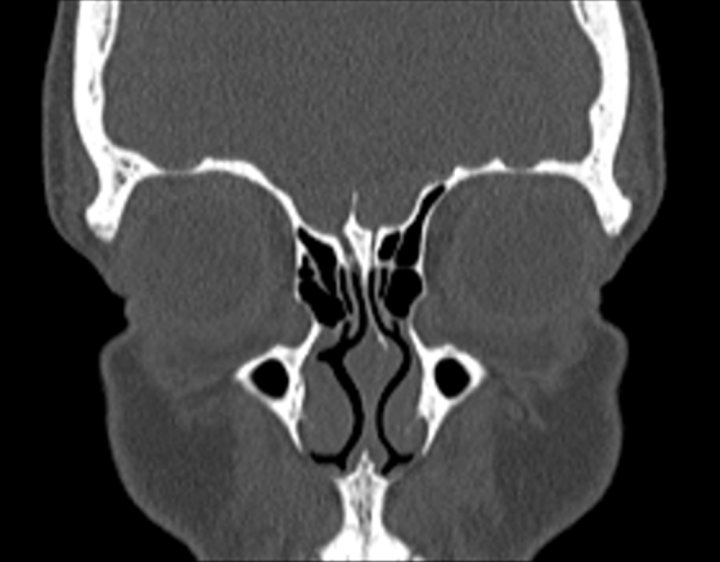

Click any image for labels.